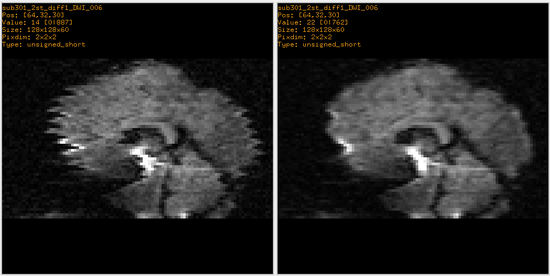

Example 1: Fixing Artifacts in DWI

The DWI data consists of 13 volumes -- a b0 and 12 gradient directions. This process was conducted 3 times per patient for a total of 39 volumes. The image below shows a particular slice in all 12 gradient directions and all 3 scans where the artifacts can clearly be seen in some of the gradient directions.

The problem can be alleviated by 2D affine registration between slices of a corrupted volume with the corresponding slice from the b0 volume, in which we assume the artifact is not present.